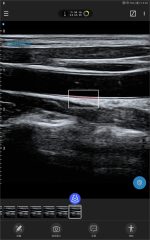

Acceso vascular (colocación de catéter central de inserción periférica (PICC), guía de punción arteriovenosa para hemodiálisis y monitorización postoperatoria)

Admite perforaciones multiángulo en el plano y perforaciones centrales fuera del plano.

Galería de demostración

|